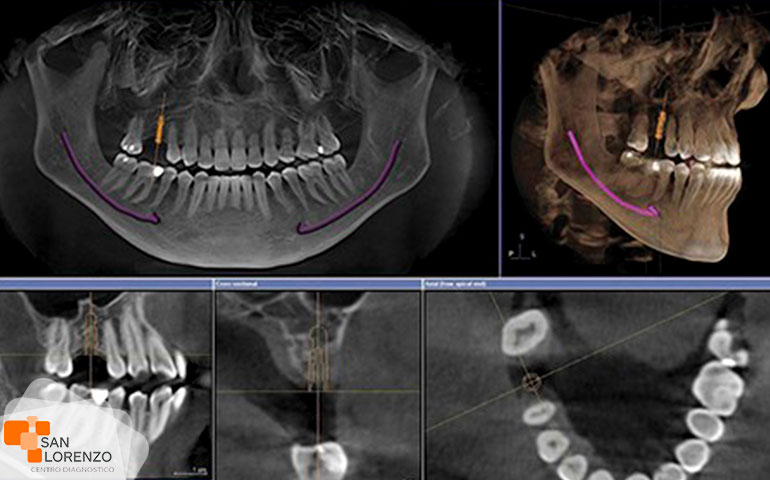

Los exámenes de imagenología que pueden incluirse para su diagnóstico pueden ser desde una radiografía, resonancia magnética, y tomografía axial computarizada. Este último tipo de examen lo aplicamos en nuestro centro de diagnóstico de calle Astorga 58 en Rancagua. En el caso de la radiología de mandíbula, es un método diagnóstico cómodo y barato. Se pueden detectar y evaluar las desviaciones en el aparato mandibular, tal estructura y función como morfología y relaciones conjuntas. En el caso de nuestro examen de escáner o tomografía axial computarizada, se utilizan como examen por lo general para establecer un diagnóstico más preciso. Actualmente, tenemos a disposición este tipo de examen de tomografía, para definir los detalles de la anatomía ósea. Este método nos ofrece imágenes con mayor detalle sobre anomalías de huesos, por mencionar algunos; la anquilosis, fracturas, tumores óseos y la artrosis.